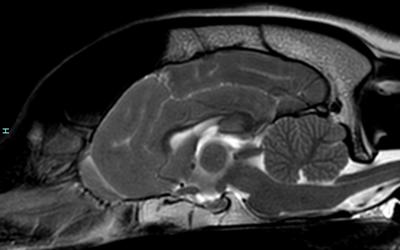

We pride ourselves on being one of the largest and most experienced neurology and neurosurgery referral teams in the UK. With a dedicated group of specialists, we cover a wide spectrum of neurology cases, ranging from routine diagnoses like epilepsy to complex procedures such as craniotomies and spinal fracture fixation.

Our expertise extends across various neurological conditions including disc extrusions, vertebral malformations, and encephalitis. With years of collective experience and support from a wide range of Veterinary Specialists in other fields, our team is well-equipped to handle even the most challenging cases with expertise and compassion.